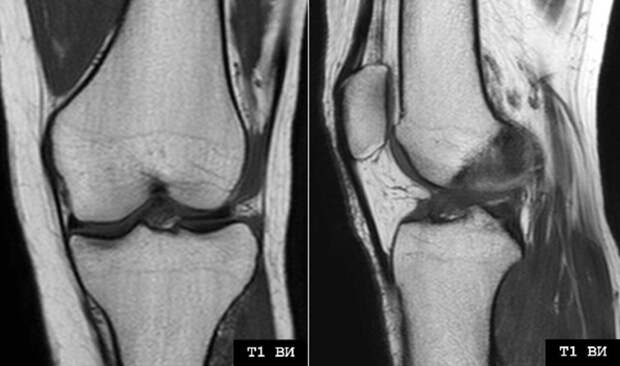

Магнитно-резонансная томография колена – это сравнительно новая методика, использующая сильное магнитное поле и радиоволны для создания подробных сканов внутренних структур сустава. Она выявляет повреждения мягких тканей, наличие воспалений, отеков, опухолей.

Это один из самых информативных способов, когда нужно оценить состояние костей и мягких тканей. Подходит для диагностики травм, хронических болезней (остеоартрит), точной оценки состояния после операций. Предоставляет изображения в различных плоскостях. Дает информацию о степени повреждения тканей. Это надо для планирования лечения, хирургического вмешательства.